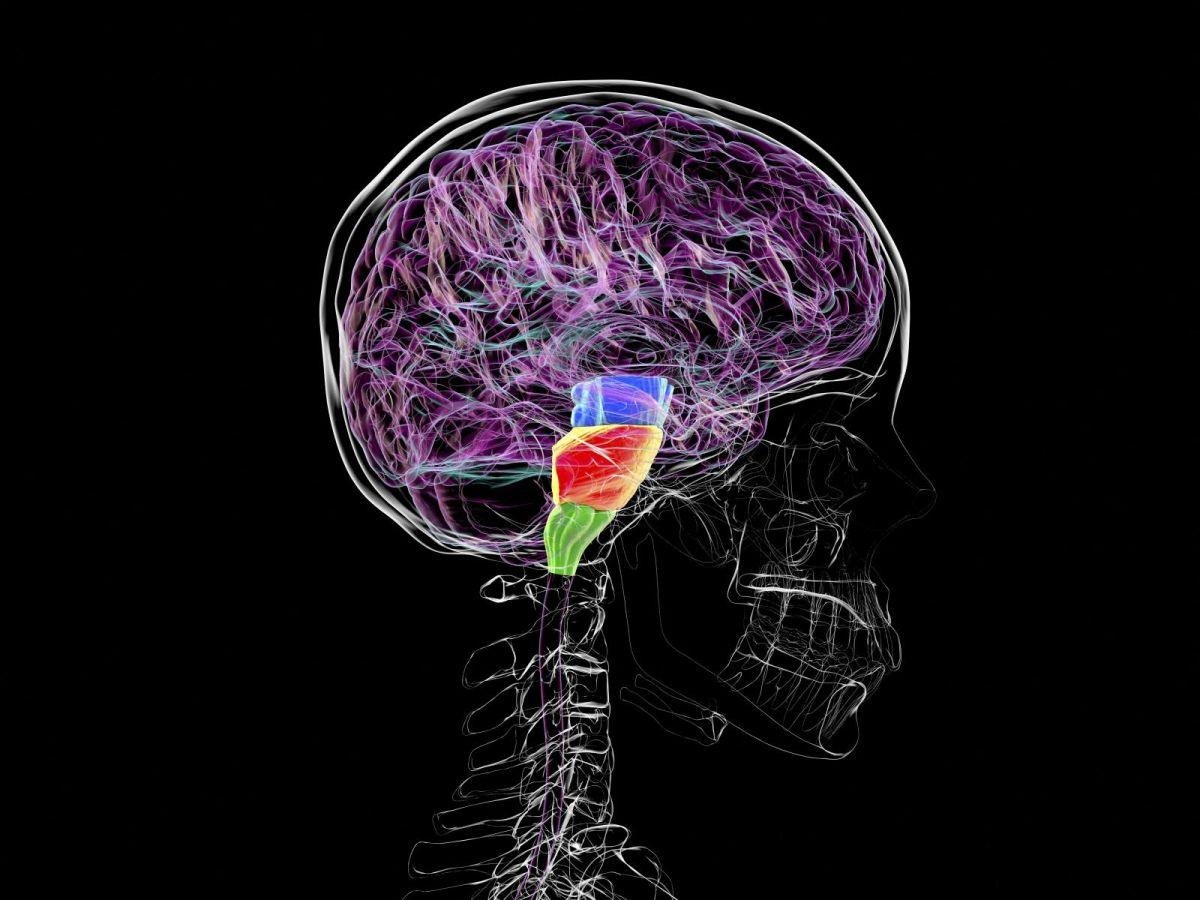

A la base de notre cerveau, l’effet placebo active des zones proches mais distinctes de quelques millimètres cubes en fonction de la localisation de la douleur (visage, bras ou jambes), démontre une étude. Stimuler précisément ces zones pourrait soulager les douleurs chroniques sans médicament.[Lire l'article en intégralité]